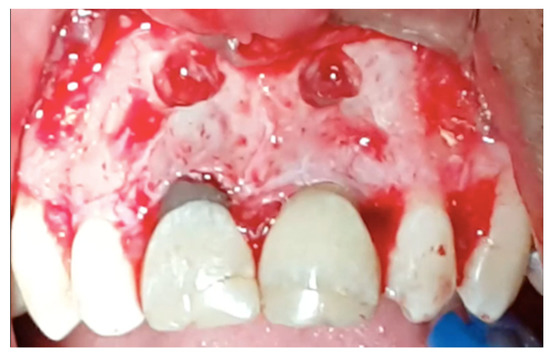

Figure 4.

The retrograde filling was performed by MTA.